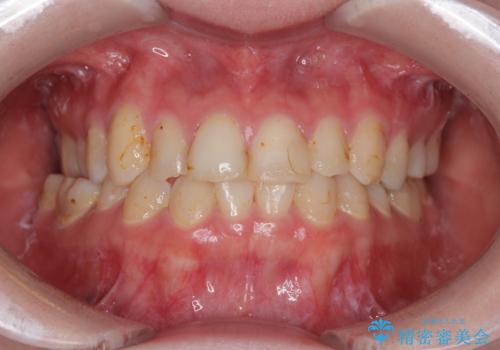

上の前歯の色味が気になる オールセラミッククラウン

- 前歯の色味が気になるとのことで来院された患者様です。今までに保険のプラスチック(コンポジットレジン)で虫歯の治療をしており経年的な劣化により着色が目立つようになっていました。また歯と歯の隣り合っているところに段差もあり虫歯になっているところもあったため前歯6本のオールセラミッククラウンによる治療を行うこととなりました。

被せものが出来上がってから数回形や色の修正がありましたが機能的にも見た目も大変満足していただきました。